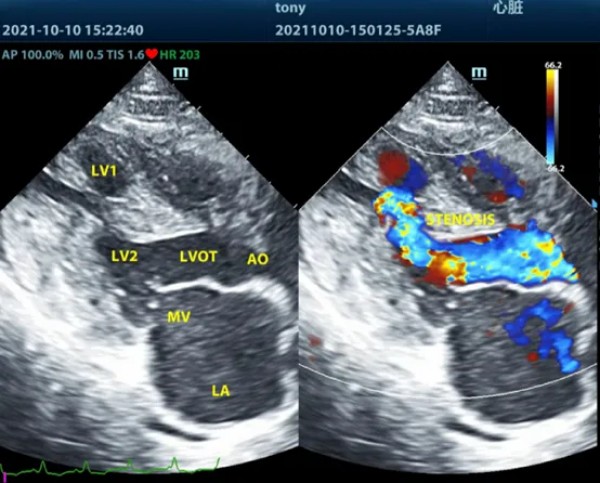

NO.2 破茧之道 技术创新与生命守护 在刘传敦院长的职业生涯中,每一个疑难病例都是对其专业能力的深度淬炼。英国短毛猫Tony心源性肺水肿的成功救治,堪称他将深厚理论功底与丰富临床经验完美结合的典范案例。 面对Tony突发的心力衰竭复发并伴随严重气道阻塞的危急病情,刘传敦院长凭借敏锐的专业判断,果断采用当时国内尚属罕见的呼吸机正压通气治疗方案。这一决策不仅需要准确把握治疗时机,更要求医生具备扎实的专业底蕴和丰富的临床经验。在治疗过程中,他通过深度镇静与气管插管的精准配合,有效清除了气道阻塞物,并借助呼吸机正压通气技术成功克服了气道阻力,为改善心功能赢得了宝贵时间。 这一成功案例的背后,是刘院长在专业领域的长期积淀。他不仅注重医疗技术的持续精进,更重视与宠物主人之间的有效沟通。治疗过程中,他通过通俗易懂的专业阐释和真诚的交流,赢得了宠物主人的理解与信任,为实施复杂治疗方案创造了必要条件。 在刘传敦院长的医学理念中,兽医工作既需要不断突破技术瓶颈,更需要始终秉持对生命的敬畏之心。他坚持以专业能力为根基,以患宠福祉为核心的行医准则,在每一个病例的救治过程中都追求精益求精。这种专业精神不仅体现在他对复杂病例的应对能力上,更渗透在他对兽医事业发展的责任担当之中。 如今,刘传敦院长依然活跃在临床诊疗一线与专业教学的前沿阵地。他的专业历程,展现了一名宠物医生通过持续学习与实践探索实现自我超越的完整轨迹,同时也为中国小动物医疗行业的专业化发展提供了值得借鉴的成长范式。在他的身上,我们看到的不仅是一位宠物医疗专业技术人才的成长,更是一种专业精神的传承与延续。